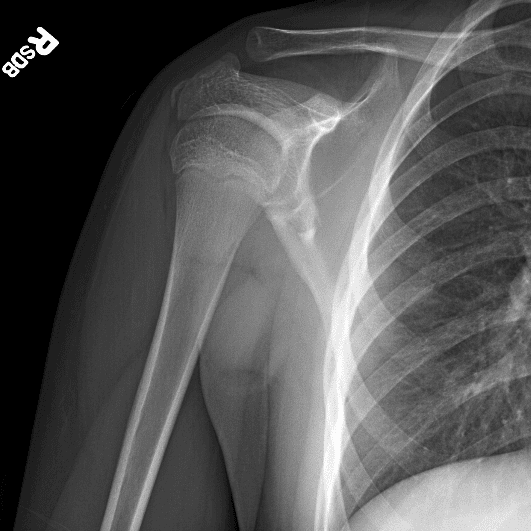

Simuliert den Dienst durch subtile oder schwierige Fälle und einige Normalbefunde.

30 Fälle